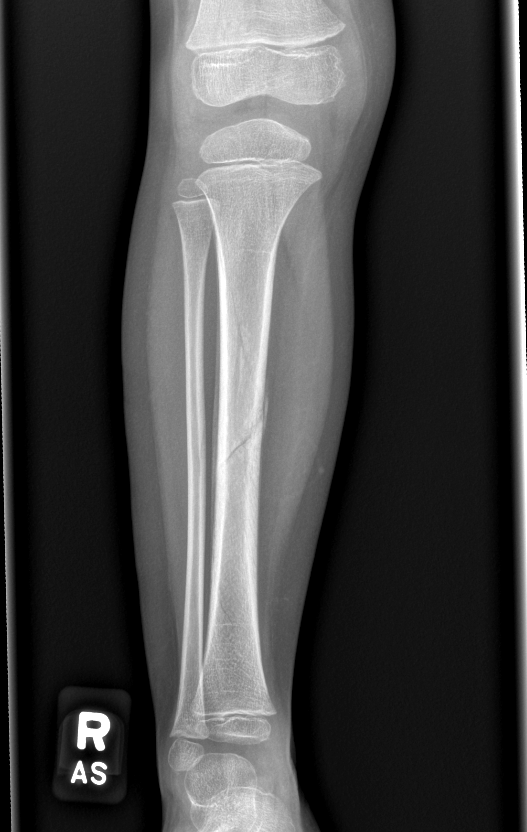

Info Images Findings Impression Reco/Acuity Case Images View Images / Launch Visage Case Notes History 2-month-old presents with decreased right arm movement, increased fussiness, and increased sleepiness for 2 days. Suspected non-accidental trauma. Exam Skeletal survey Prior Study none Dicom View Reference Material

Section 1 Submit Findings CB1550 Findings Skeletal Survey - Technique Check Skull AP/Lat Yes No Cervical and Thoracolumbar spine Yes No Chest X-Ray Yes No Ribs – Left/Right Oblique Yes No Abdominal X-Ray Yes No Pelvis with both hips Yes No Bilateral Humerus, Forearm, Hand Yes No Bilateral Femur, Tibia/fibula, feet Yes No Any additional lateral views of the extremities Yes No The exam is over or under penetrated. Yes No The exam may or may not be limited by overlying structures or soft tissues, body habitus, patient positioning, support devices, or motion. Yes No The area of concern is indicated by the patient, technologist, or care provider. Yes No The area of concern is included on the exam. Yes No Soft Tissues There is soft tissue swelling, indistinctness of fat/muscle planes, gas, or laceration in the area of clinical concern. Yes No There is an effusion, fat pad displacement, or fat fluid level. Yes No There is a radiodense or lucent foreign body. Yes No There are other densities, calcifications, post-surgical changes, or support devices in the soft tissues. Yes No Any support lines/tubes. Yes No Bone There is a break or interruption of the continuity of the cortical or cancellous bone. Yes No There is overriding of the trabeculae with apparent sclerosis. Yes No There is displacement of a fracture fragment. Yes No There is bowing of the bone in addition to the fracture at the apex of the bowed bone concerning for the greenstick. Yes No There is a spiral fracture of the leg concerning for toddler’s fracture. Yes No There is abnormal angulation or bulging of the cortical surface relative to the normal cortex which could be from a buckle or torus fracture. Yes No There is a displaced fragment which may be from avulsion by a tendon, ligament, or joint capsule or from a comminuted or other fracture. Yes No The stress trabeculae or other trabeculae of the cancellous bone are interrupted or otherwise abnormal. Yes No There is subperiosteal or endosteal reaction which could indicate a healing or subacute fracture or other abnormality. Yes No There is hard/soft callus formation. Yes No There is remodeling of the bone. Yes No There is a corner fracture or metaphyseal lesion that could be from nonaccidental trauma. Yes No There are multiple fractures of different ages. Yes No There are vertebral body/spinous process fractures. Yes No There are rib fractures. Location - posterior or lateral. Yes No There is scapular/sternal fracture. Yes No There are fractures of the digits. Yes No There are wormian bones. Yes No There are intrasutural bones. Yes No There is metaphyseal abnormality (lucencies, increased density, erosion) which may be from something other than injury such as stress, metabolic disease (e.g. rickets with loss or distortion of the zone of the provisional calcification), neoplasm (e.g. leukemia), heavy metals, inflammation, or infection. Yes No There are metaphyseal spurs. Yes No There are bony deformities involving multiple bones. Yes No The bones are gracile. Yes No There are non-healing fractures. Yes No There is/are focal or multifocal lytic/lucent, blastic/sclerotic or mixed density lesion(s) or other abnormality. Yes No Overall bone density is increased or decreased with or without thinning or thickening of the cortical or cancellous bone. Yes No Growth plates, ossification centers, apophyses The growth plate(s) is/are abnormal. Yes No There is widening of the physis from a fracture with or without displacement of the epiphysis (Salter-Harris I). Yes No There is a fracture through the physis which then extends into the metaphysis with or without angulation or displacement (S-H II). Yes No There is a fracture through the physis which then extends into the epiphysis and is intra-articular, with or without angulation or displacement (S-H III). Yes No There is a fracture through the metaphysis, physis, and epiphysis which extends into the joint space with or without angulation or displacement (S-H IV). Yes No There is narrowing of the physis from a compression fracture (S-H V). Yes No The apophysis, epicondyle, secondary ossification center, or accessory ossicle is displaced or otherwise abnormal. Yes No The ossification centers are underdeveloped. Yes No Joints and alignment There is an effusion, fat pad displacement, or fat fluid level. Yes No The epiphysis or subchondral bone is fractured, interrupted, flattened, compressed, impacted, displaced, or otherwise abnormal. Yes No There is an intra-articular loose body or chondrocalcinosis. Yes No The joint is widened, narrowed, dislocated, malaligned, or incongruent. Yes No There is pseudoarthrosis. Yes No Other findings There are developmental changes or other anatomic variants or other existing conditions that may or may not be contributing to symptoms which can or should be further evaluated non-emergently or are otherwise incidental. Yes No The remainder of the exam is abnormal for age. Yes No The lungs show focal airspace opacity. Yes No There is pneumothorax. Yes No There is organomegaly. Yes No There is intra-abdominal calcification. Yes No There is displacement of the bowel loops. Yes No There is free intraperitoneal air. Yes No The bowel loops are dilated/obstructed. Yes No There is paraspinal soft tissue abnormality. Yes No